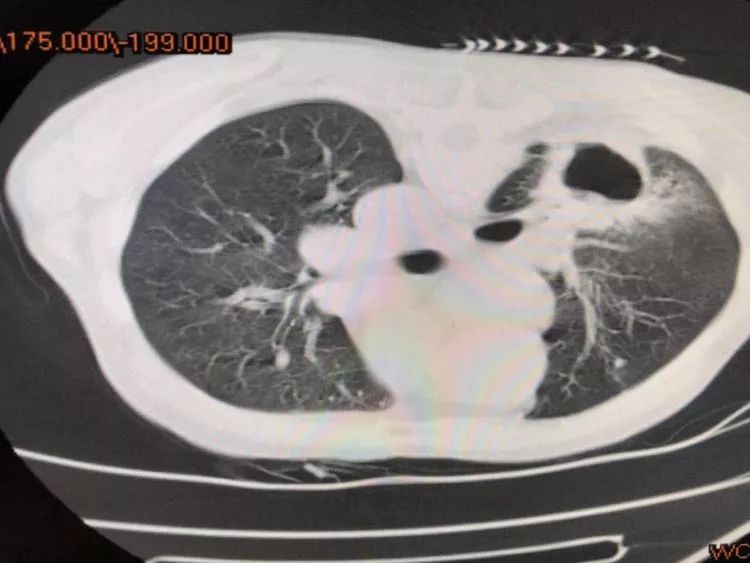

第一例 79岁的陈爷爷来省胸科医院就诊,经检查胸部CT厚壁空洞,气管镜检查提示外压性狭窄,为明确诊断,肺穿刺是最佳选择,通过CT引导,洞壁取材。

从影像学上考虑肿瘤的可能性更大,一般空洞我们多考虑鳞癌,可是,病理报告告诉我们,腺癌也可以形成大空洞,同时患者椎体MRI提示骨转移,错失最佳治疗时机。